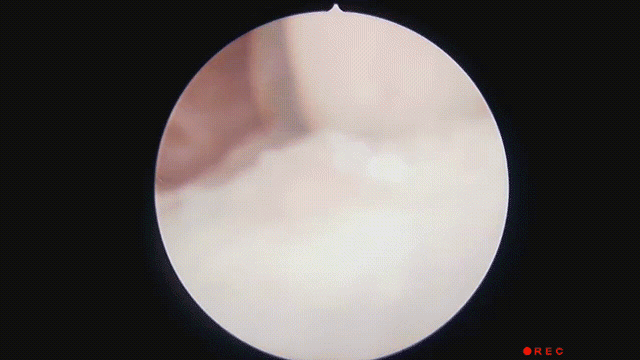

示意图

接诊的大夫看了一眼没有发现鱼刺,也没看到任何异物。此时女子已经呼吸困难,颈部也肿胀影响正常呼吸。

因为找不到病因,医生只能给她做了全方位的CT扫描,结果就在女子的颈部肌肉里看到了一根长约5厘米的鱼刺。

正是这根鱼刺引发女子颈部脓肿和呼吸道阻塞,差点让她在急诊室的众目睽睽之下死的不明不白。

医生看到鱼刺后也吓了一跳,马上安排女子服用消炎抗生素并接受手术。术后五天,女子才平安出院。

中国医生一击即中的拔鱼刺手艺